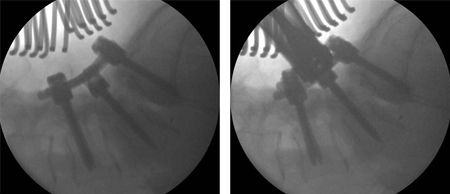

[Figure caption and citation for the preceding image starts]: Spondylolisthesis: flexion/extension viewsFrom the collection of Dr N. Quiraishi [Citation ends].

[Figure caption and citation for the preceding image starts]: Intra-operative images showing a gradual reduction of the deformity: L4 to S1 instrumented fusion, transforaminal fusion at L5S1 and bilateral L5 decompressionFrom the collection of Dr N. Quiraishi [Citation ends].